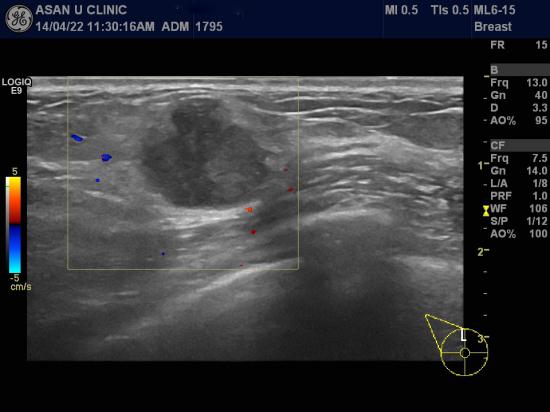

아산유외과 개원 후 92번째 유방암진단.

50세 여성분입니다.

우측 유방에 몽울이 만져져 내원하여 유방초음파와 조직검사 실시하여

겨드랑이에 림프절 비대 없는 침윤성 유관암으로 진단되셨습니다.

정기적인 건강검진으로

건강하고 행복한 삶을 보내시길 바랍니다.